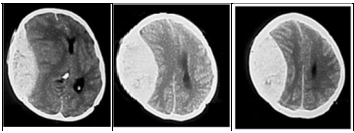

Um homem de 35 anos de idade foi vítima de acidente automobilístico e encaminhado ao pronto-socorro. Na admissão, estava consciente, comunicativo, com hálito etílico e com períodos confusionais e de agitação, mas movimentava todos os quatro membros sem deficits e deambulava. Não guardava nenhuma recordação do acidente (escala de coma de Glasgow = 14 pontos). Havia contusões no couro cabeludo e fratura da clavícula direita. Seis horas após a admissão, o paciente encontrava-se sonolento e respondendo mal aos comandos verbais (escala de coma de Glasgow = 11 pontos). As principais imagens do exame de tomografia computadorizada cranioencefálica (TC) sem contraste são mostradas abaixo.

Enunciado 3511089-1

Cortes axiais de TC de crânio sem contraste

Com base na história clínica, na evolução neurológica e no exame de neuroimagem desse caso hipotético, é correto afirmar que o diagnóstico é o de